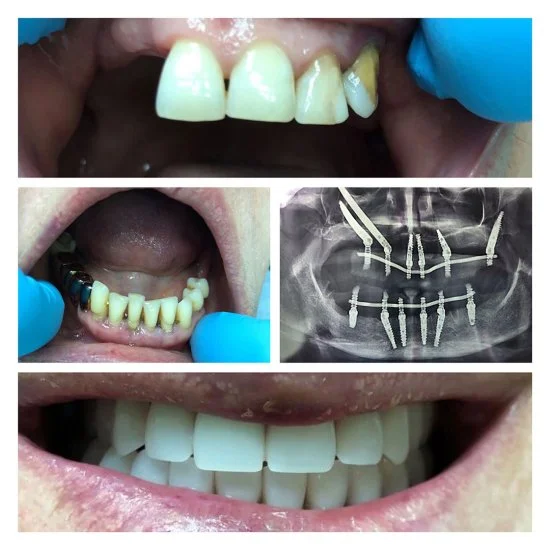

Andrey to doświadczony chirurg stomatolog z ponad 24-letnim stażem. Zajmuje się usuwaniem zębów i implantacją także w trudnych przypadkach — nawet wtedy, gdy inni lekarze nie podejmują się leczenia. Dzięki wiedzy i praktyce potrafi przeprowadzić skomplikowane zabiegi tak, żeby efekt był pewny i przewidywalny.